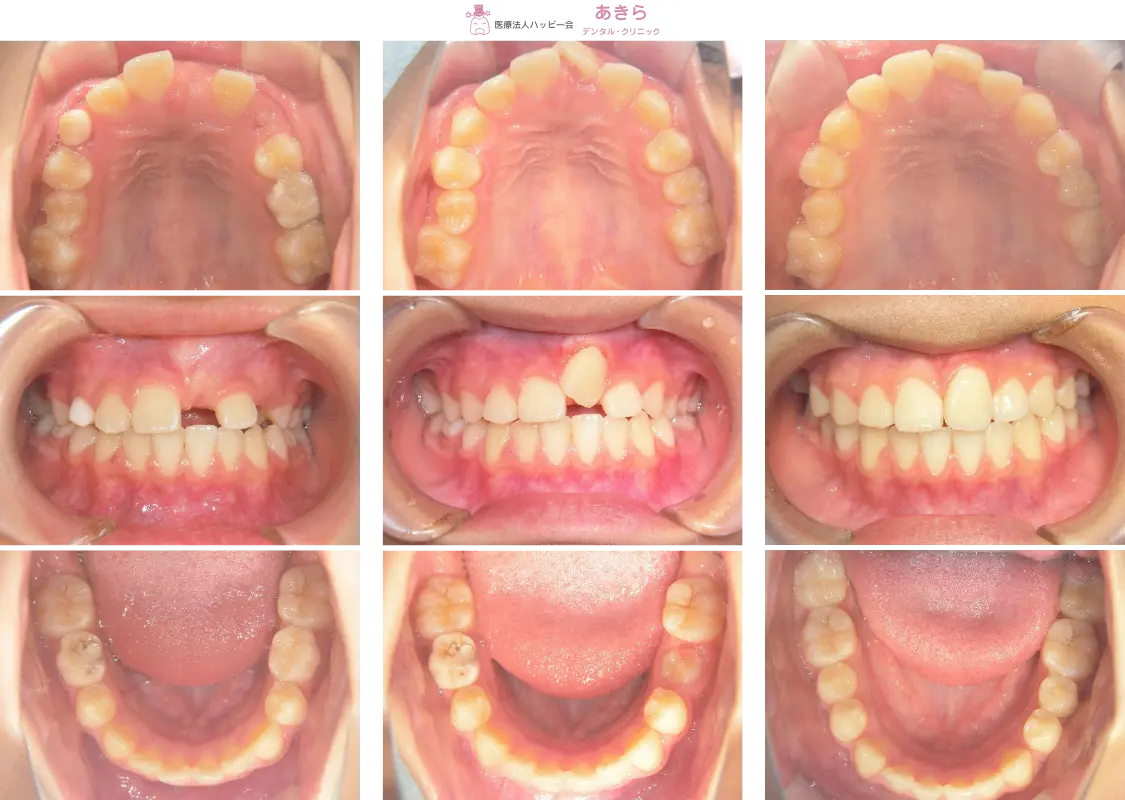

2019年4月6日 初診時口腔内写真

※経過…┗1番開窓&牽引(2019年)

2019年10月6日 口腔内写真

2019年11月29日 口腔内写真(SH装置スタート)